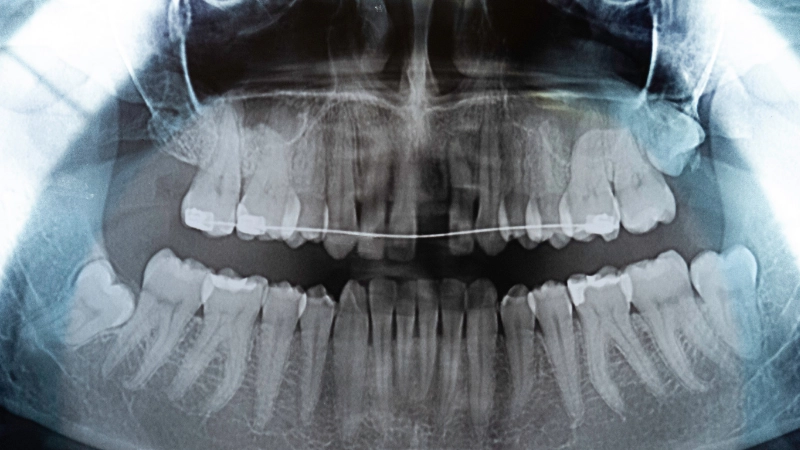

Không phải tất cả các trường hợp niềng răng đều cần nhổ răng khôn. Việc có chỉ định nhổ hay không phụ thuộc vào tình trạng răng miệng, hướng mọc của răng khôn và kế hoạch chỉnh nha cụ thể. Trong thực tế, bác sĩ thường cân nhắc nhổ răng khôn trong hai trường hợp sau:

Trường hợp 1: Răng khôn mọc lệch, mọc ngầm, đâm vào má hoặc chèn ép răng số 7. Trong những trường hợp này, răng khôn có thể gây đau nhức, viêm nhiễm và ảnh hưởng đến sự ổn định của cung hàm. Do răng khôn có thể mọc trong hoặc sau quá trình niềng răng, việc nhổ răng khôn sớm giúp hạn chế nguy cơ răng khôn xô đẩy các răng khác, làm ảnh hưởng đến kết quả chỉnh nha.

Trường hợp 2: Một số trường hợp đặc biệt, bác sĩ có thể chỉ định nhổ răng khôn nhằm tạo khoảng trống hỗ trợ chỉnh nha, thay vì nhổ răng số 4. Do răng khôn nằm ở vị trí trong cùng của cung hàm, việc nhổ răng này thường không ảnh hưởng đến thẩm mỹ, tuy nhiên cần được cân nhắc kỹ lưỡng và chỉ định rõ ràng từ bác sĩ chuyên khoa.

Tuy nhiên, không phải trường hợp nào cũng cần nhổ răng khôn, việc chỉ định nhổ cần được bác sĩ chuyên khoa thăm khám và đánh giá kỹ lưỡng dựa trên tình trạng răng miệng, hướng mọc của răng khôn và phác đồ chỉnh nha của từng người.

Tại Răng Hàm Mặt Hồng Ngọc, khách hàng được thăm khám trực tiếp với bác sĩ chuyên khoa Răng Hàm Mặt và chỉnh nha, kết hợp chụp phim và phân tích cấu trúc hàm nhằm đưa ra chỉ định phù hợp, đồng thời xây dựng phác đồ điều trị cá nhân hóa, đảm bảo hiệu quả và tính ổn định lâu dài.